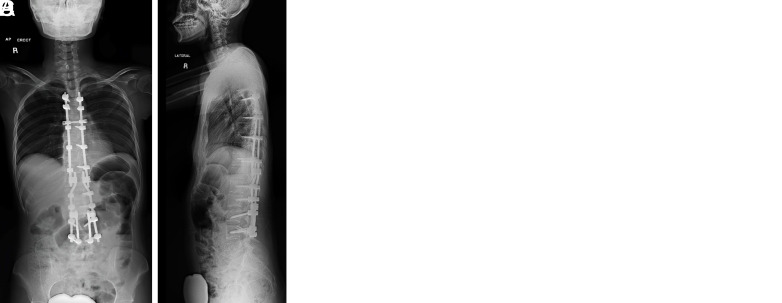

The incidence of traumatic spine fractures (TSF) is increasing worldwide, with a reported annual incidence of up to 32.8 per 100000 persons. However, there are only a few cases of spine fractures reported in adolescent idiopathic scoliosis (AIS) patients after posterior spinal fusion (PSF) in the literature. Fractures adjacent to fusion blocks that extend into the lower lumbar spine pose a unique challenge as stabilization of such fractures might require an extension of instrumentation to L5 or the pelvis. We report a novel surgical technique where bilateral pedicle and cortical screws at L4 and supplementary rods that connect the cortical screws to the main rods via dominos were implemented for optimizing the distal anchorage for TSF stabilization following an L3 Chance fracture in an AIS patient who had undergone T4-L2 posterior spinal fusion.